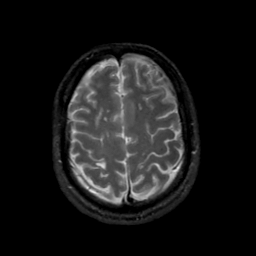

MR Study #17, July 7, 1991 -- Slice #39

[Home][Help][Clinical][Tour 1][Tour 2] Slice 39